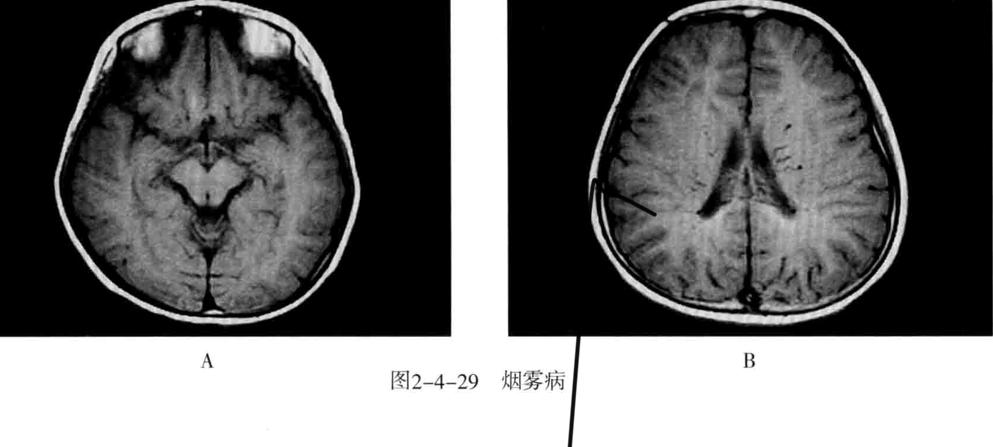

十、烟雾病

又称为脑底异常血管网症、脑底动脉环闭塞症。是以脑内虹吸段至大脑前、中动脉近端狭窄或闭塞,同时伴有广泛侧支循环形成,导致颅底出现异常毛细血管网为特征的脑血管病。好发年龄10岁以下和40-50岁。临床表现为脑缺血和脑出血两大类。儿童多为颈内动脉系统缺血性改变,成人多为颅内出血。

1. CT平扫表现为双侧额叶、顶叶及颞叶皮质或皮质下区多发脑梗死及脑萎缩改变,也可以出现颅内出血。增强有时可见到颈内动脉及大脑前中动脉粗细明显不对称,或者充盈不良,甚至不显影。可显示基底池及基底节区的侧支循环网,大多表现为为不规则的扭曲成团的强化血管影。

2. MRI表现为脑缺血引起的T1WI低、T2WI高信号脑梗死区,颈内动脉及大脑中动脉主干的“流空效应”变弱或消失,异常血管网在T2WI上表现为基底节区和鞍上池内多发细小血管影,呈网状低信号或无信号区。皮质侧支循环形成时,增强扫描可见皮质血管增多、扩张、强化、呈“常春藤征”。

3. MRA可直接显示颈内动脉、大脑前、中动脉狭窄或闭塞,于颅底见烟雾状异常血管网,常可见到颈外动脉和椎-基底动脉分支代偿性增粗。

4. 脑血管造影是确诊烟雾病的主要检查方法,可显示狭窄或闭塞的动脉及异常扩张的血管网。